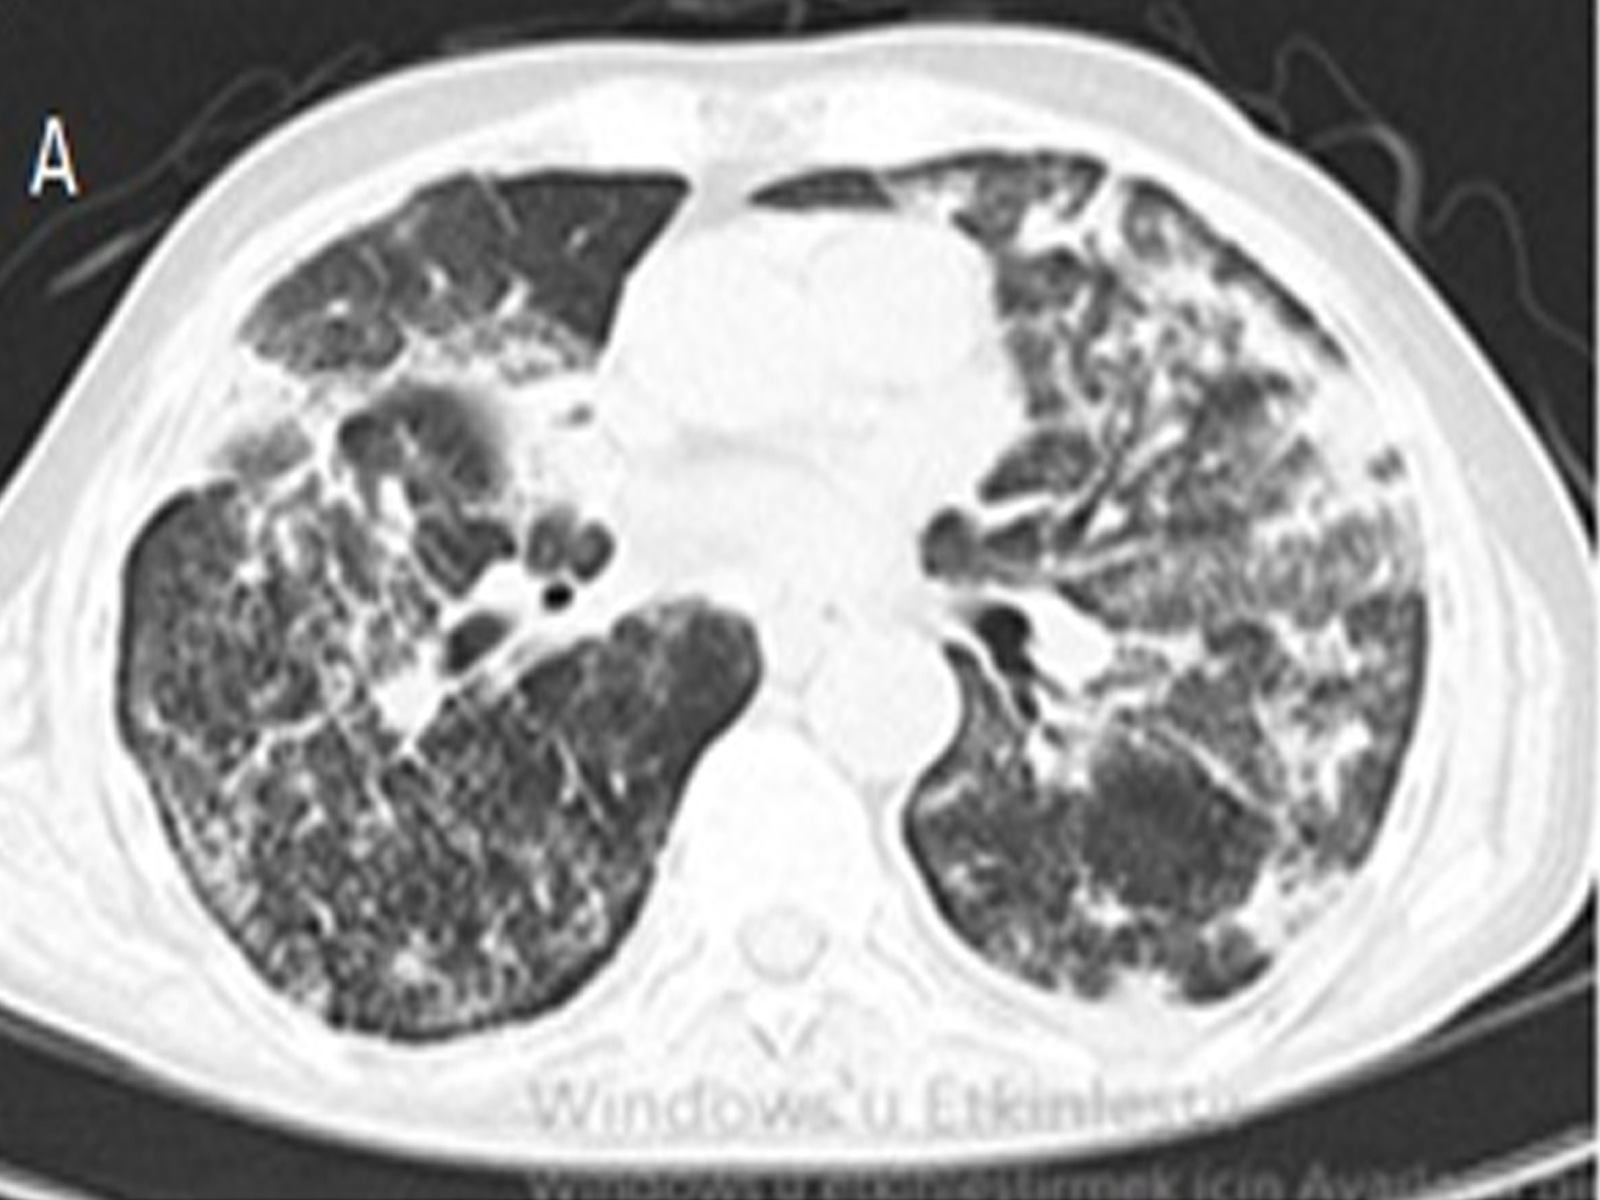

Acute Eosinophilic Pneumonia as a Rare Cause of Acute Onset Respiratory Failure

Mustafa Nadir Tantay, Kutay Arkoç, Damla Serçe Unat, Ahmet Emin Erbaycu doi: 10.5505/respircase.2026.09581 Pages 38 - 42 |